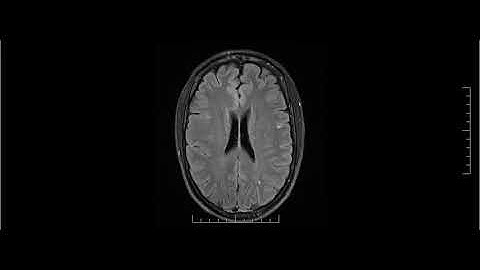

Recovery from PML and residual deficits